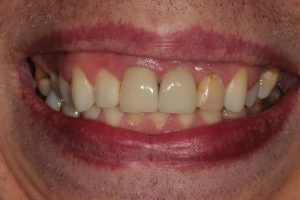

Upper Front Tooth Implant

This patient had broken their upper front tooth and the exisitng dental crown had fallen off. The underlying root was unfortunatley irreparable.

The dental root was subsequently removed and an implant placed at the same time. The implant had a temporary crown placedon the same day.

The ‘After’ photos shows the final crown that was made after 3 months. The implant crown was made to match the form and colour of the exisiting teeth to give an overall natural aesthetic finish.